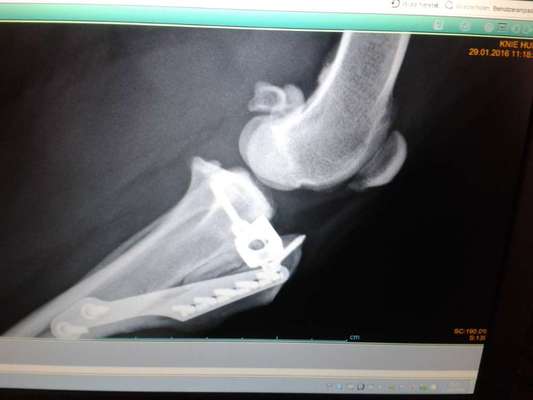

So sieht das aus